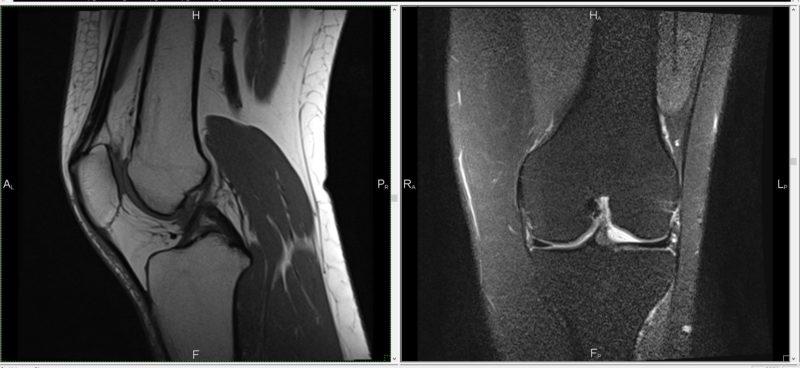

Что показывает исследование

Существует прямая связь между тем, что демонстрирует МРТ коленного сустава, и процессом его проведения. Данное исследование способно обнаружить разрыв мениска. На снимках МРТ мениск будет представлен с нечеткими контурами, в то время как у здорового коленного сустава он выглядит как четкий черный треугольник.

МРТ также может выявить как растяжение, так и разрыв связок. При этом аппарат способен зафиксировать как частичный, так и полный разрыв. Исследование позволяет обнаружить наличие жидкости в области связок коленного сустава. МРТ эффективно фиксирует дистрофические изменения в хрящах, что с высокой степенью точности помогает диагностировать артроз суставов у пациента.

Кроме того, метод позволяет оценить степень отека. Он более точно выявляет наличие опухолей в колене, даже когда у пациента еще нет явных признаков их появления.